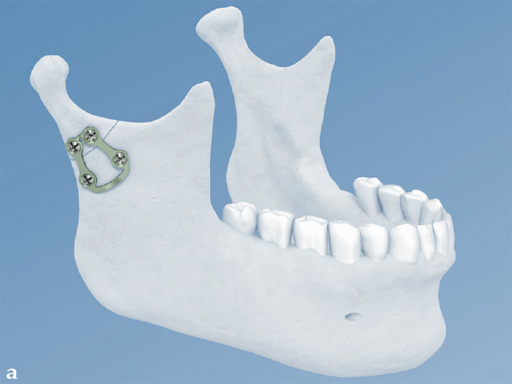

Trapezoidal Plate

The trapezoidal plate is designed to fit the region of the condylar base and provides improved strength and stability over previous single-bar plate designs, thereby eliminating the need to place two plates. It is precontoured to account for the curvature in the transition zone between the base of the condylar process and the adjacent neck. The location of screw holes enables plates to straddle the mandibular foramen and the adjacent canal inlet, thereby avoiding accidental nerve injury. The trapezoidal plate can be applied using external and transoral surgical approaches. If required a transbuccal cannula can be centered in the countersunk screw holes for proper drilling alignment.